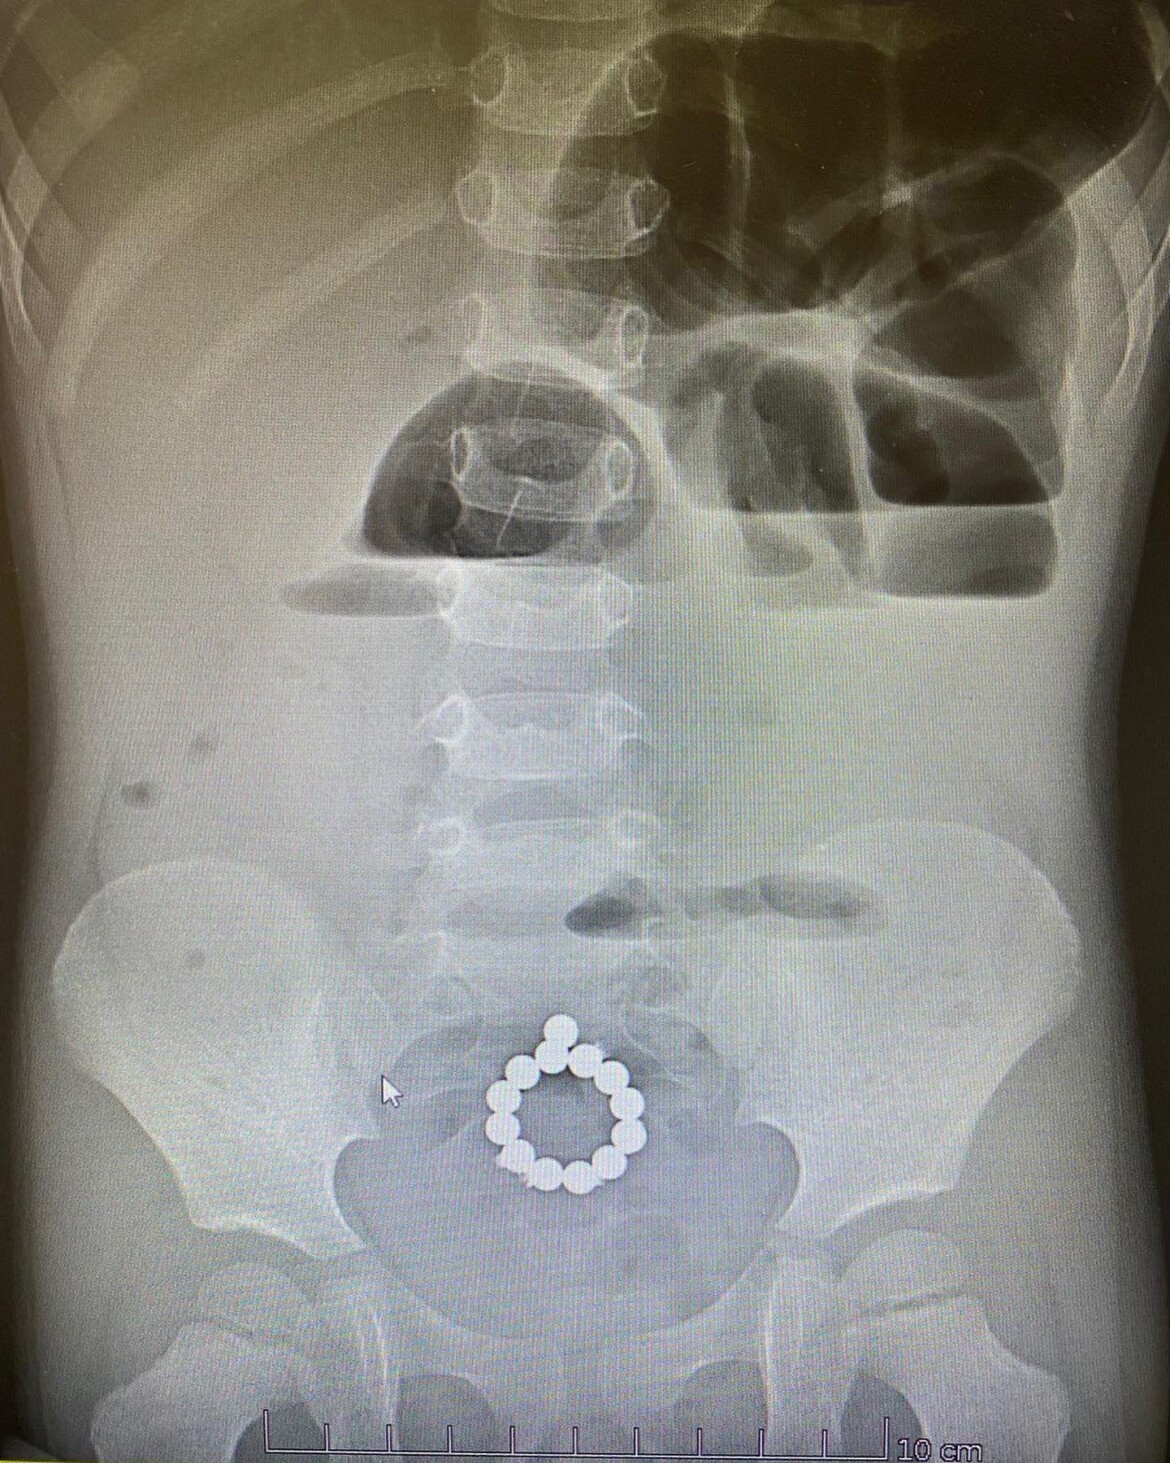

Детские хирурги Камского детского медцентра достали из желудка ребенка 40 магнитных шариков. Ему провели эндоскопическую операцию. После проведенного лечения ребенка выписали домой.

Это уже второй случай в этом медцентре за год, когда дети глотают большое количество магнитов. Те же хирурги спасли девочку, которая проглотила 13 магнитов-шариков. В ее случае магниты прошли по желудочно-кишечному тракту, притянулись друг к другу и образовали цепочку-кольцо вокруг кишечника.

Фото: пресс-служба Минздрава РТ